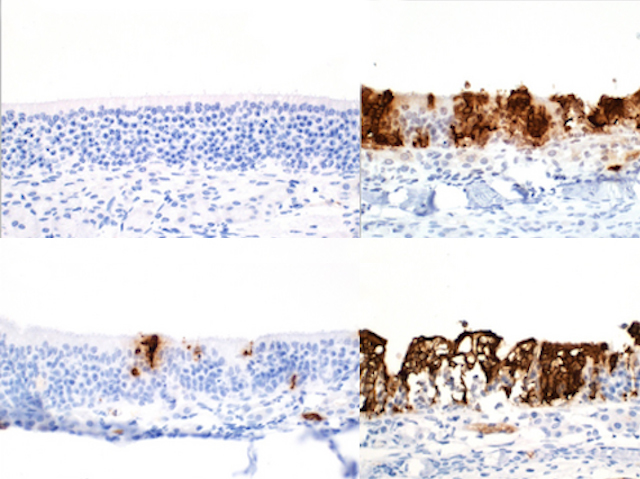

Vaccines are typically injected into an arm muscle, including those recently developed against SARS-CoV-2, the virus responsible for COVID-19. Yet coronaviruses first infect the mucous membranes in our respiratory tract, in the nose, mouth, throat and lungs. Administering vaccines intranasally, to target those frontline areas, could allow us to respond to infection faster. Nasal vaccines against SARS-CoV-2 have already been developed in India and China, but researchers are now testing a new intranasal live-attenuated vaccine, containing a modified virus. Tests in hamsters found it highly effective: very few SARS-CoV-2 particles (in brown) penetrated their nasal mucous membranes after double vaccination with the intranasal vaccine (top left) or even a combination of one intranasal dose with an existing mRNA vaccine (bottom left), compared to poor results after intramuscular vaccination only (right-hand panels). Following up these encouraging results with safety and efficacy trials in humans could provide new options for future vaccination.